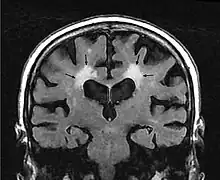

En la Tomografía Computarizada, la leucoaraiosis se observa como regiones con menor densidad, mas oscuras que las circundantes, es decir áreas hipodensas, en Imagen por Resonancia Magnética se define como lesiones con mayor intensidad de señal es decir áreas hiperintensas, por presentar un aspecto más brillante que las zonas aledañas. Estas imágenes pueden verse en las regiones próximas a los ventrículos cerebrales, corona radiata y centro semioval.[9] Se han utilizado escalas cualitativas como la de Fazekas para determinar el grado de las lesiones: